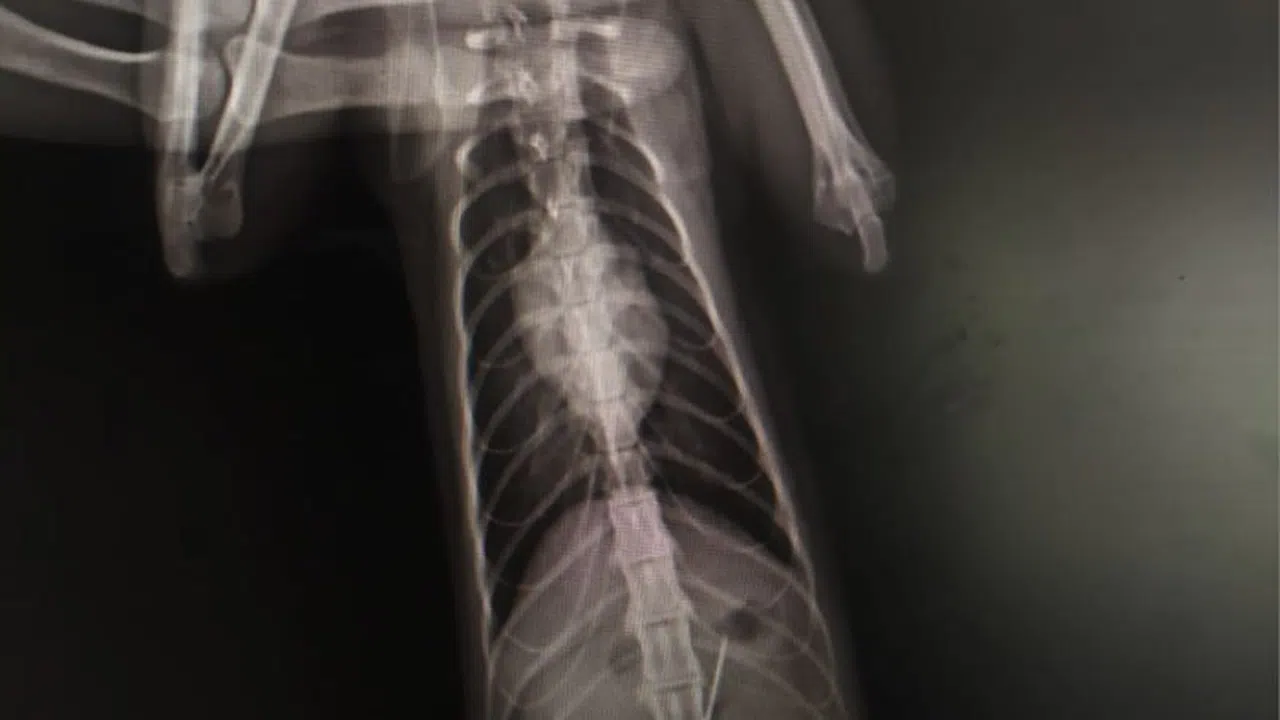

Kentte bulunan özel bir veteriner kliniğinde muayene edilen kedinin röntgeni çekildi.

Kedinin midesinde tespit edilen dikiş iğnesi endoskopiyle çıkarıldı.